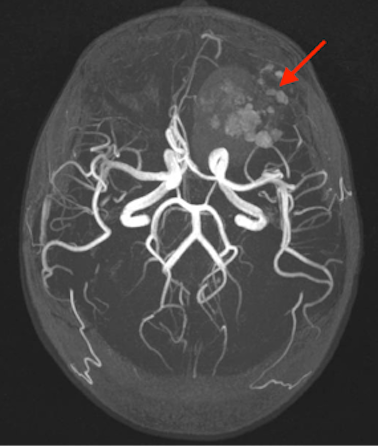

Gli esami ematici risultano nella norma, ma gli esami di imaging neuroradiologico (RM encefalo e angioRM) rivelano la presenza di cavernomi cerebrali multipli, uno più voluminoso in sede frontale sinistro con recente sanguinamento, associato a edema e discreto effetto massa (Figura 1 e 2)). Necessario quindi trasferimento in Neurochirurgia per intervento e in programma consulenza genetica.